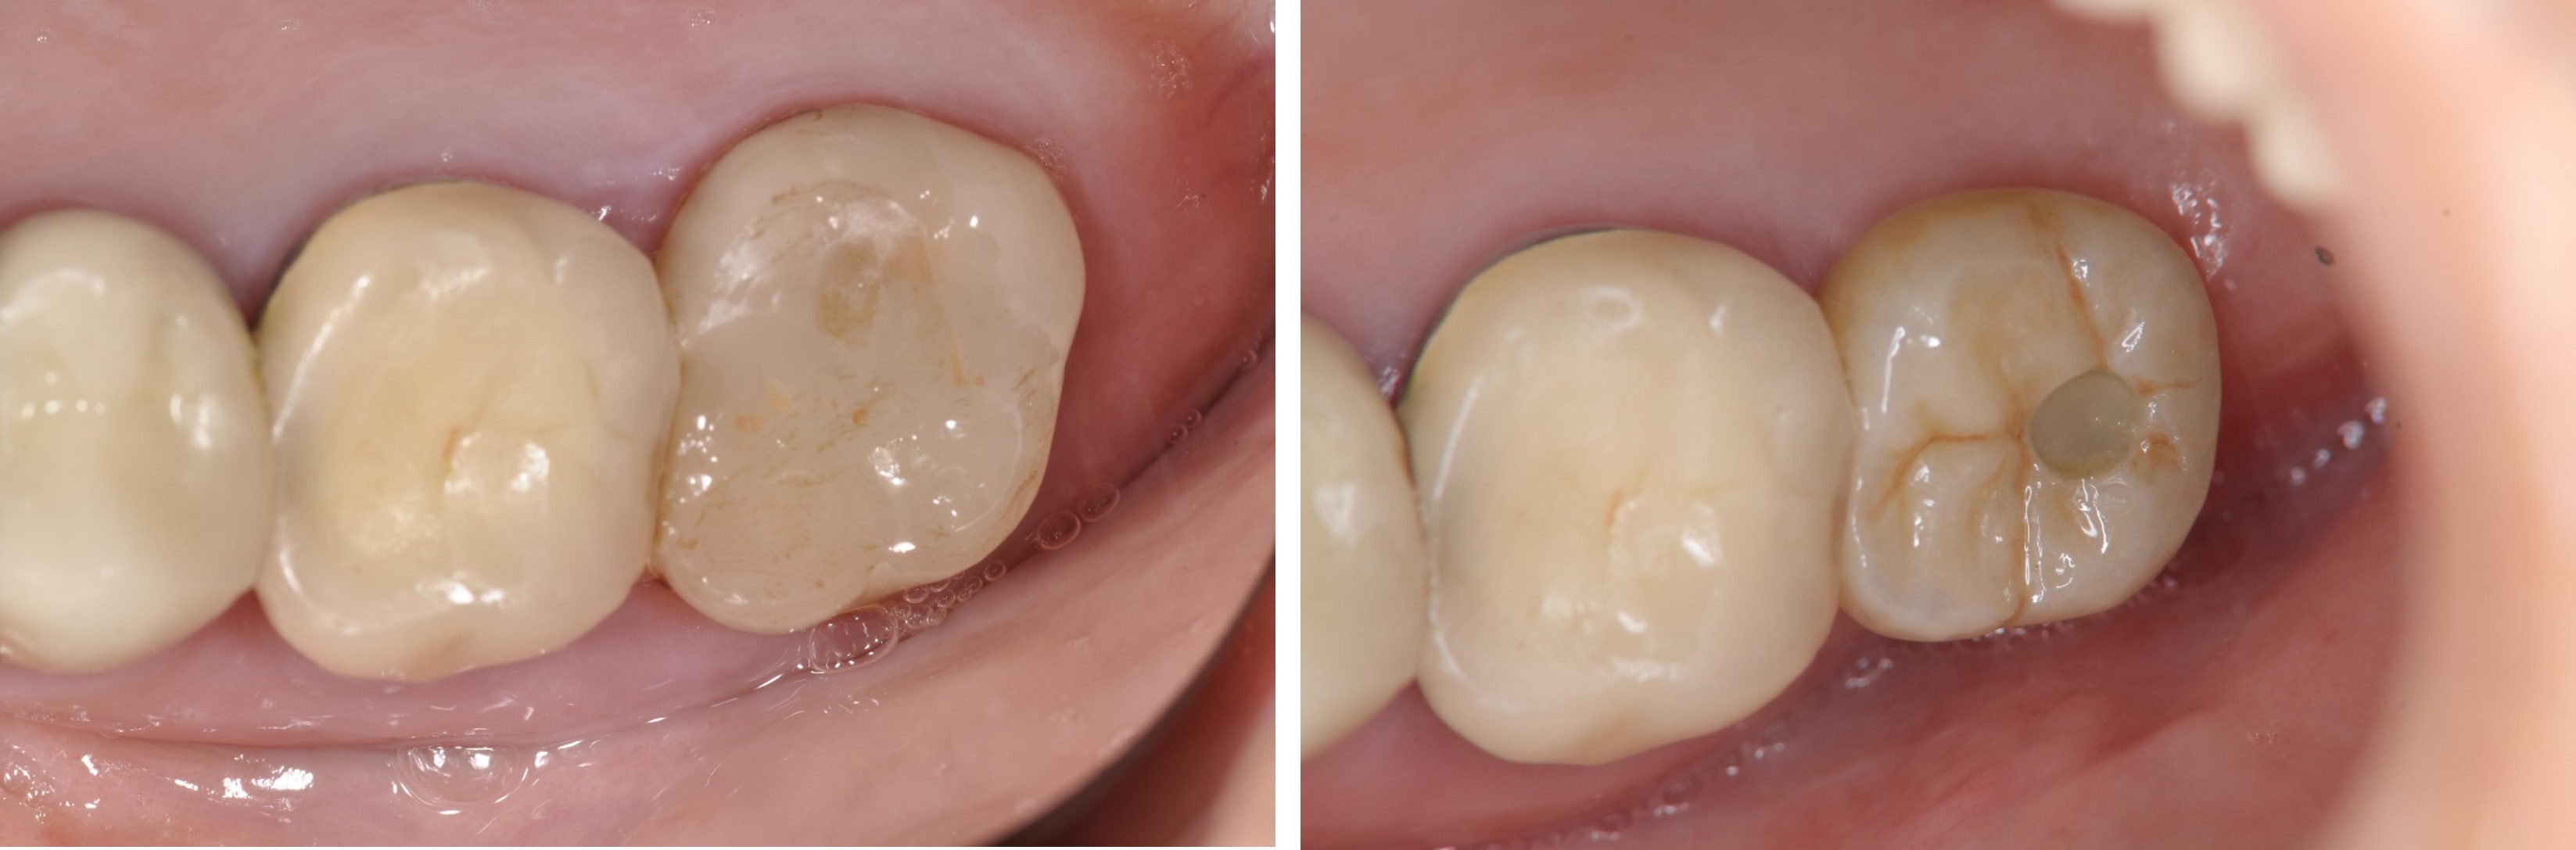

陶瓷崁體-二次蛀牙-#3646

審美牙科

瓷塊-崁體